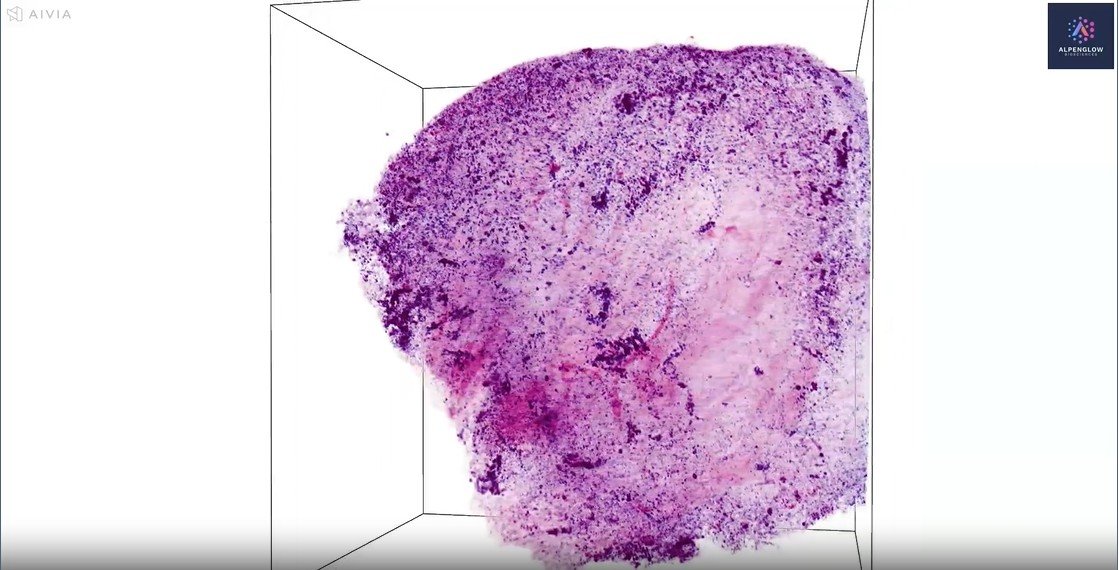

Low-resolution imaging of a human dorsal root ganglion (DRG) sample

This video presents low-resolution (scout) imaging of a human dorsal root ganglion (DRG) sample provided by AnaBios. The sample features computational H&E staining, with ToPro-3 highlighting nuclei and Eosin-capturing protein structures.